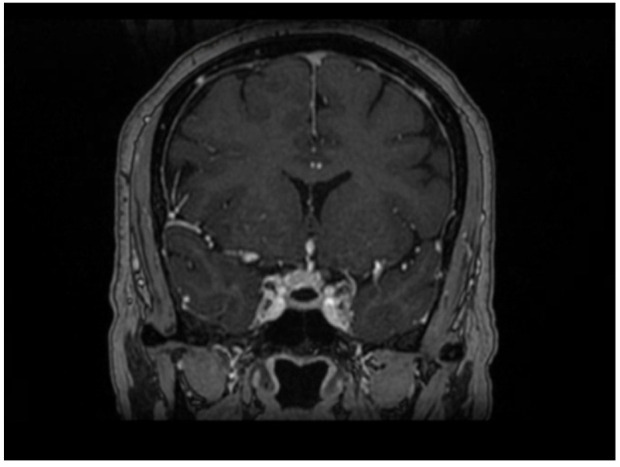

Tuberculum sellae meningioma (TSM) is an uncommon tumor among all intracranial meningiomas. As these tumors grow, they compress the surrounding structures, including the optic nerves and the pituitary gland. Ocular motor nerve palsy (OMNP) can occur as an isolated mononeuropathy or as part of multiple cranial nerve palsies. The role of corticosteroids in the management of OMNP has not been fully studied in the literature. In this report, we present a case of a previously well middle-aged woman who presented with severe headache and isolated OMNP on examination. MRI of the brain showed a small TSM that extends into the right optic canal. In our case, we noted the expedient and complete recovery of isolated OMNP within a few days following treatment with dexamethasone. This case report is on an isolated OMNP associated with TSM, which has not been previously reported. In addition, it highlights the role of corticosteroids in achieving rapid recovery from OMNP.